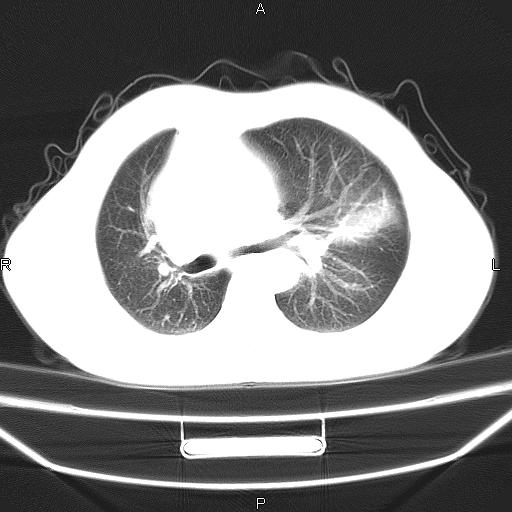

患者,男。50岁。近几日有咳嗽症状,无其他不适,既往病史无,考虑膈疝。请前辈们看看指导指导。

膈膨升,左下肺通气不良,膈肌好像还完整。

考虑左侧膈疝。

左侧膈疝。

符合隔膨升,膈肌较完整。